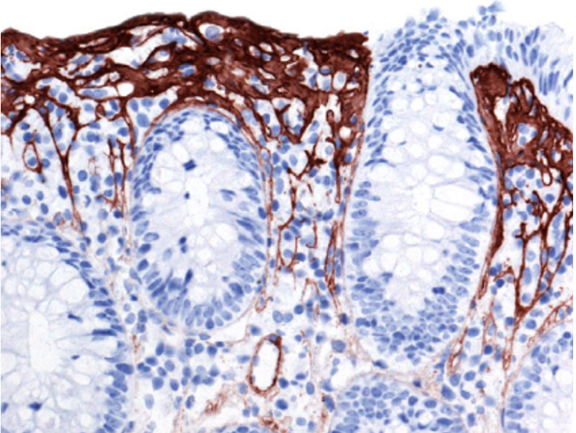

Vad visar kolonbiopsin?

Vad ser du på den uppförstorade biopsin?